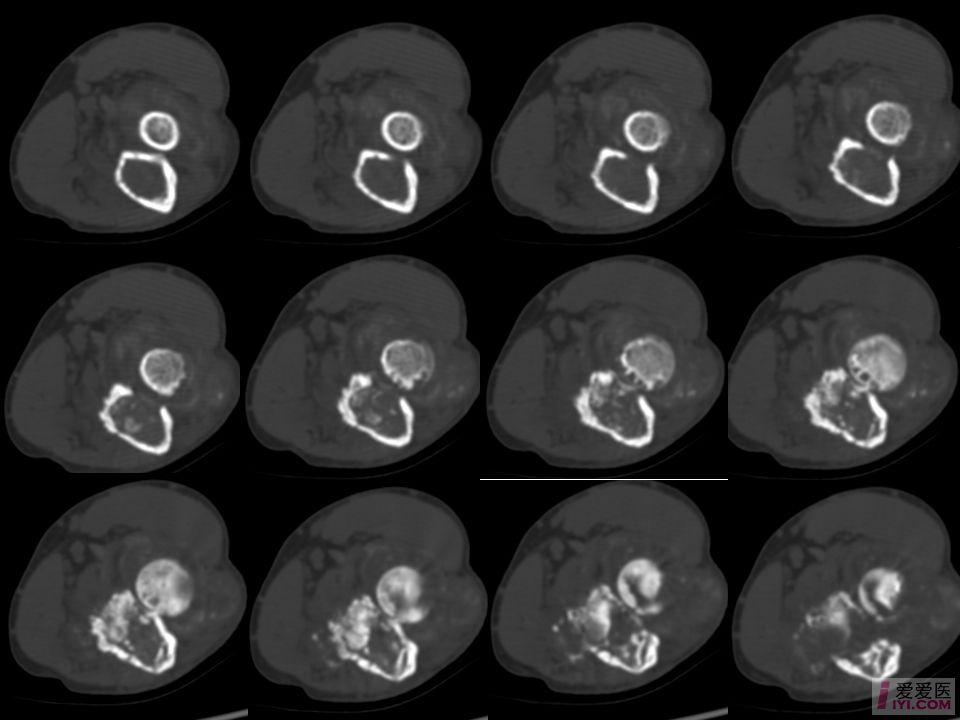

足部ct平扫摆位

足部ct平扫摆位,足部ct平扫图片

足部ct平扫图片

足ct平扫

正常足部ct

足ct扫描定位线图片

足部ct断层解剖图

脚部ct

正常右脚骨ct图

正常脚骨CT图

脚上的CT正常的片子